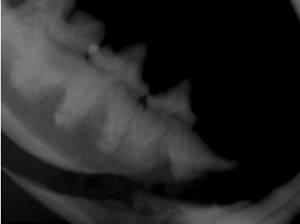

Cone Beam Computed Tomography

The Center now provides advanced imaging via cone beam CT. Cone beam CT is excellent for visualization of bony structures of the skull, nasal cavity, teeth, and ears. Cone beam CT is especially helpful for diagnosing dental disease and evaluation of jaw fractures. It can also be useful for evaluating the sinuses and tympanic bulla. Cone beam CT can be used in conjunction with nasal biopsy and culture to evaluate nasal discharge whether chronic or acute.